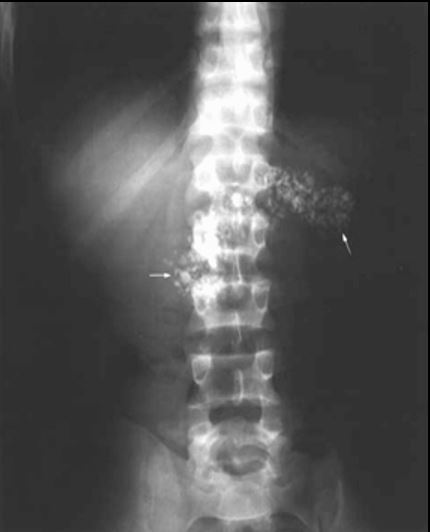

DOR LOMBAR BILATERAL, MAIS INTENSA

À DIREITA.

NOME DO EXAME?

NOME DA INCIDÊNCIA?

ACHADOS?

DIAGNÓSTICO?

A

RD SIMPLES DO ABDOME.

DECÚBITO DORSAL

IMAGEM CÁLCICA VOLUMOSA NO HIPOCÔNDRIO ESQUERDO MOLDANDO PELVE E CÁLICES. HÁ OUTRA IMAGEM CÁLCICA À DIREITA EM PROJEÇÃO URETERAL ( NÍVEL DE L3)

CÁLCULO CORALIFORME À ESQ E CÁLCULO URETERAL À DIREITA.